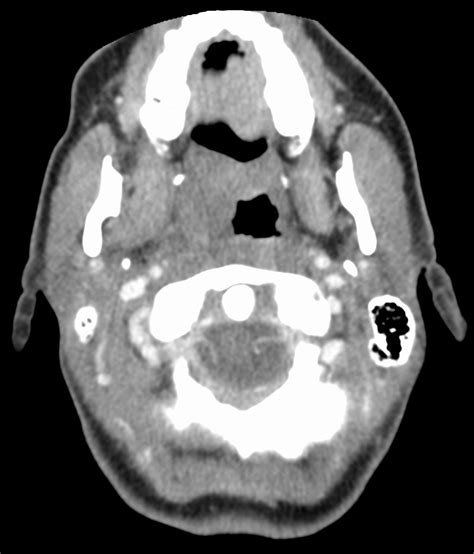

Alright, let’s get down to the nitty-gritty of fatty tissue , also known medically as adipose tissue. It’s a natural part of our bodies, guys, playing a crucial role in insulation, energy storage, and protecting our organs. However, when we’re talking about a CT scan showing “FF positive,” it means that this fatty tissue is showing up in a location that raises a question for the radiologist. CT scans work by using X-rays to create detailed cross-sectional images of your body. Different tissues absorb X-rays at different rates, and this information is used to construct the images. Fatty tissue has a particular density that shows up distinctly on these scans, often appearing darker than other tissues like muscle or bone. So, when the CT scan detects this signature of fatty tissue in an area where it’s not supposed to be, it gets flagged as “FF positive.” This isn’t a disease in itself, but rather a finding . The significance of this finding entirely depends on where this fat is located. For instance, finding fat in the abdomen is perfectly normal, but finding it in the chest cavity, within a bone, or in an unexpected organ could indicate various conditions that need further evaluation. Your doctor and the radiologist will consider the exact location and appearance of this fat, along with your medical history and other symptoms, to determine the next steps. It’s this unexpected location that’s the key takeaway here. We’re not talking about the general layer of fat under your skin, but rather discrete collections of fat in anatomical spaces where you wouldn’t normally expect them. This is why the interpretation is so crucial and why further investigation is often recommended to ensure a comprehensive understanding of your health status. The subtlety of these findings underscores the importance of expert interpretation in radiology, where even seemingly small deviations can hold significant diagnostic value, guiding subsequent clinical decisions and patient care pathways effectively.

Now, let’s talk about what “FF” might actually mean in this context. While “FF positive” most commonly relates to the presence of fatty tissue, the exact abbreviation can sometimes vary slightly depending on the specific radiology department or the software used. However, for the most part, you can assume it’s pointing towards fat . So, where might this unexpected fat be found, and what could it signify? One common scenario is the detection of intramuscular fat . This means fat has infiltrated the muscle tissue itself. This can happen due to various reasons, including aging, disuse of the muscle (like after an injury or prolonged bed rest), or certain medical conditions like obesity or metabolic disorders. Another possibility is fat found within the peritoneum , the lining of the abdominal cavity. While some omental fat (fat attached to the intestines) is normal, excessive or oddly distributed fat here could be noted. Perhaps one of the more significant areas where an “FF positive” finding might warrant close attention is in the chest cavity . Finding fatty tissue in the chest, outside of its normal locations like the mediastinum (the space between the lungs), could potentially be related to conditions like lipomas (benign fatty tumors) or, less commonly, other types of lesions. Similarly, if fat is detected within or near bones , it might be related to benign conditions like lipomas within the bone marrow or, again, other abnormalities that require differentiation. It’s also possible, though less frequent, for “FF positive” to refer to other findings, so always clarify with your doctor. The key is that the radiologist has identified a density consistent with fat in a place that deviates from the standard anatomical expectation. This prompts further review to ascertain the nature and significance of this finding. They’ll be looking at the size, shape, borders, and exact location of the fat deposit to decide if it’s benign or if further workup is needed. It’s this detailed analysis that helps distinguish between a harmless incidental finding and something that might require treatment or monitoring, ensuring you get the most accurate diagnosis and appropriate care pathway tailored to your specific situation.